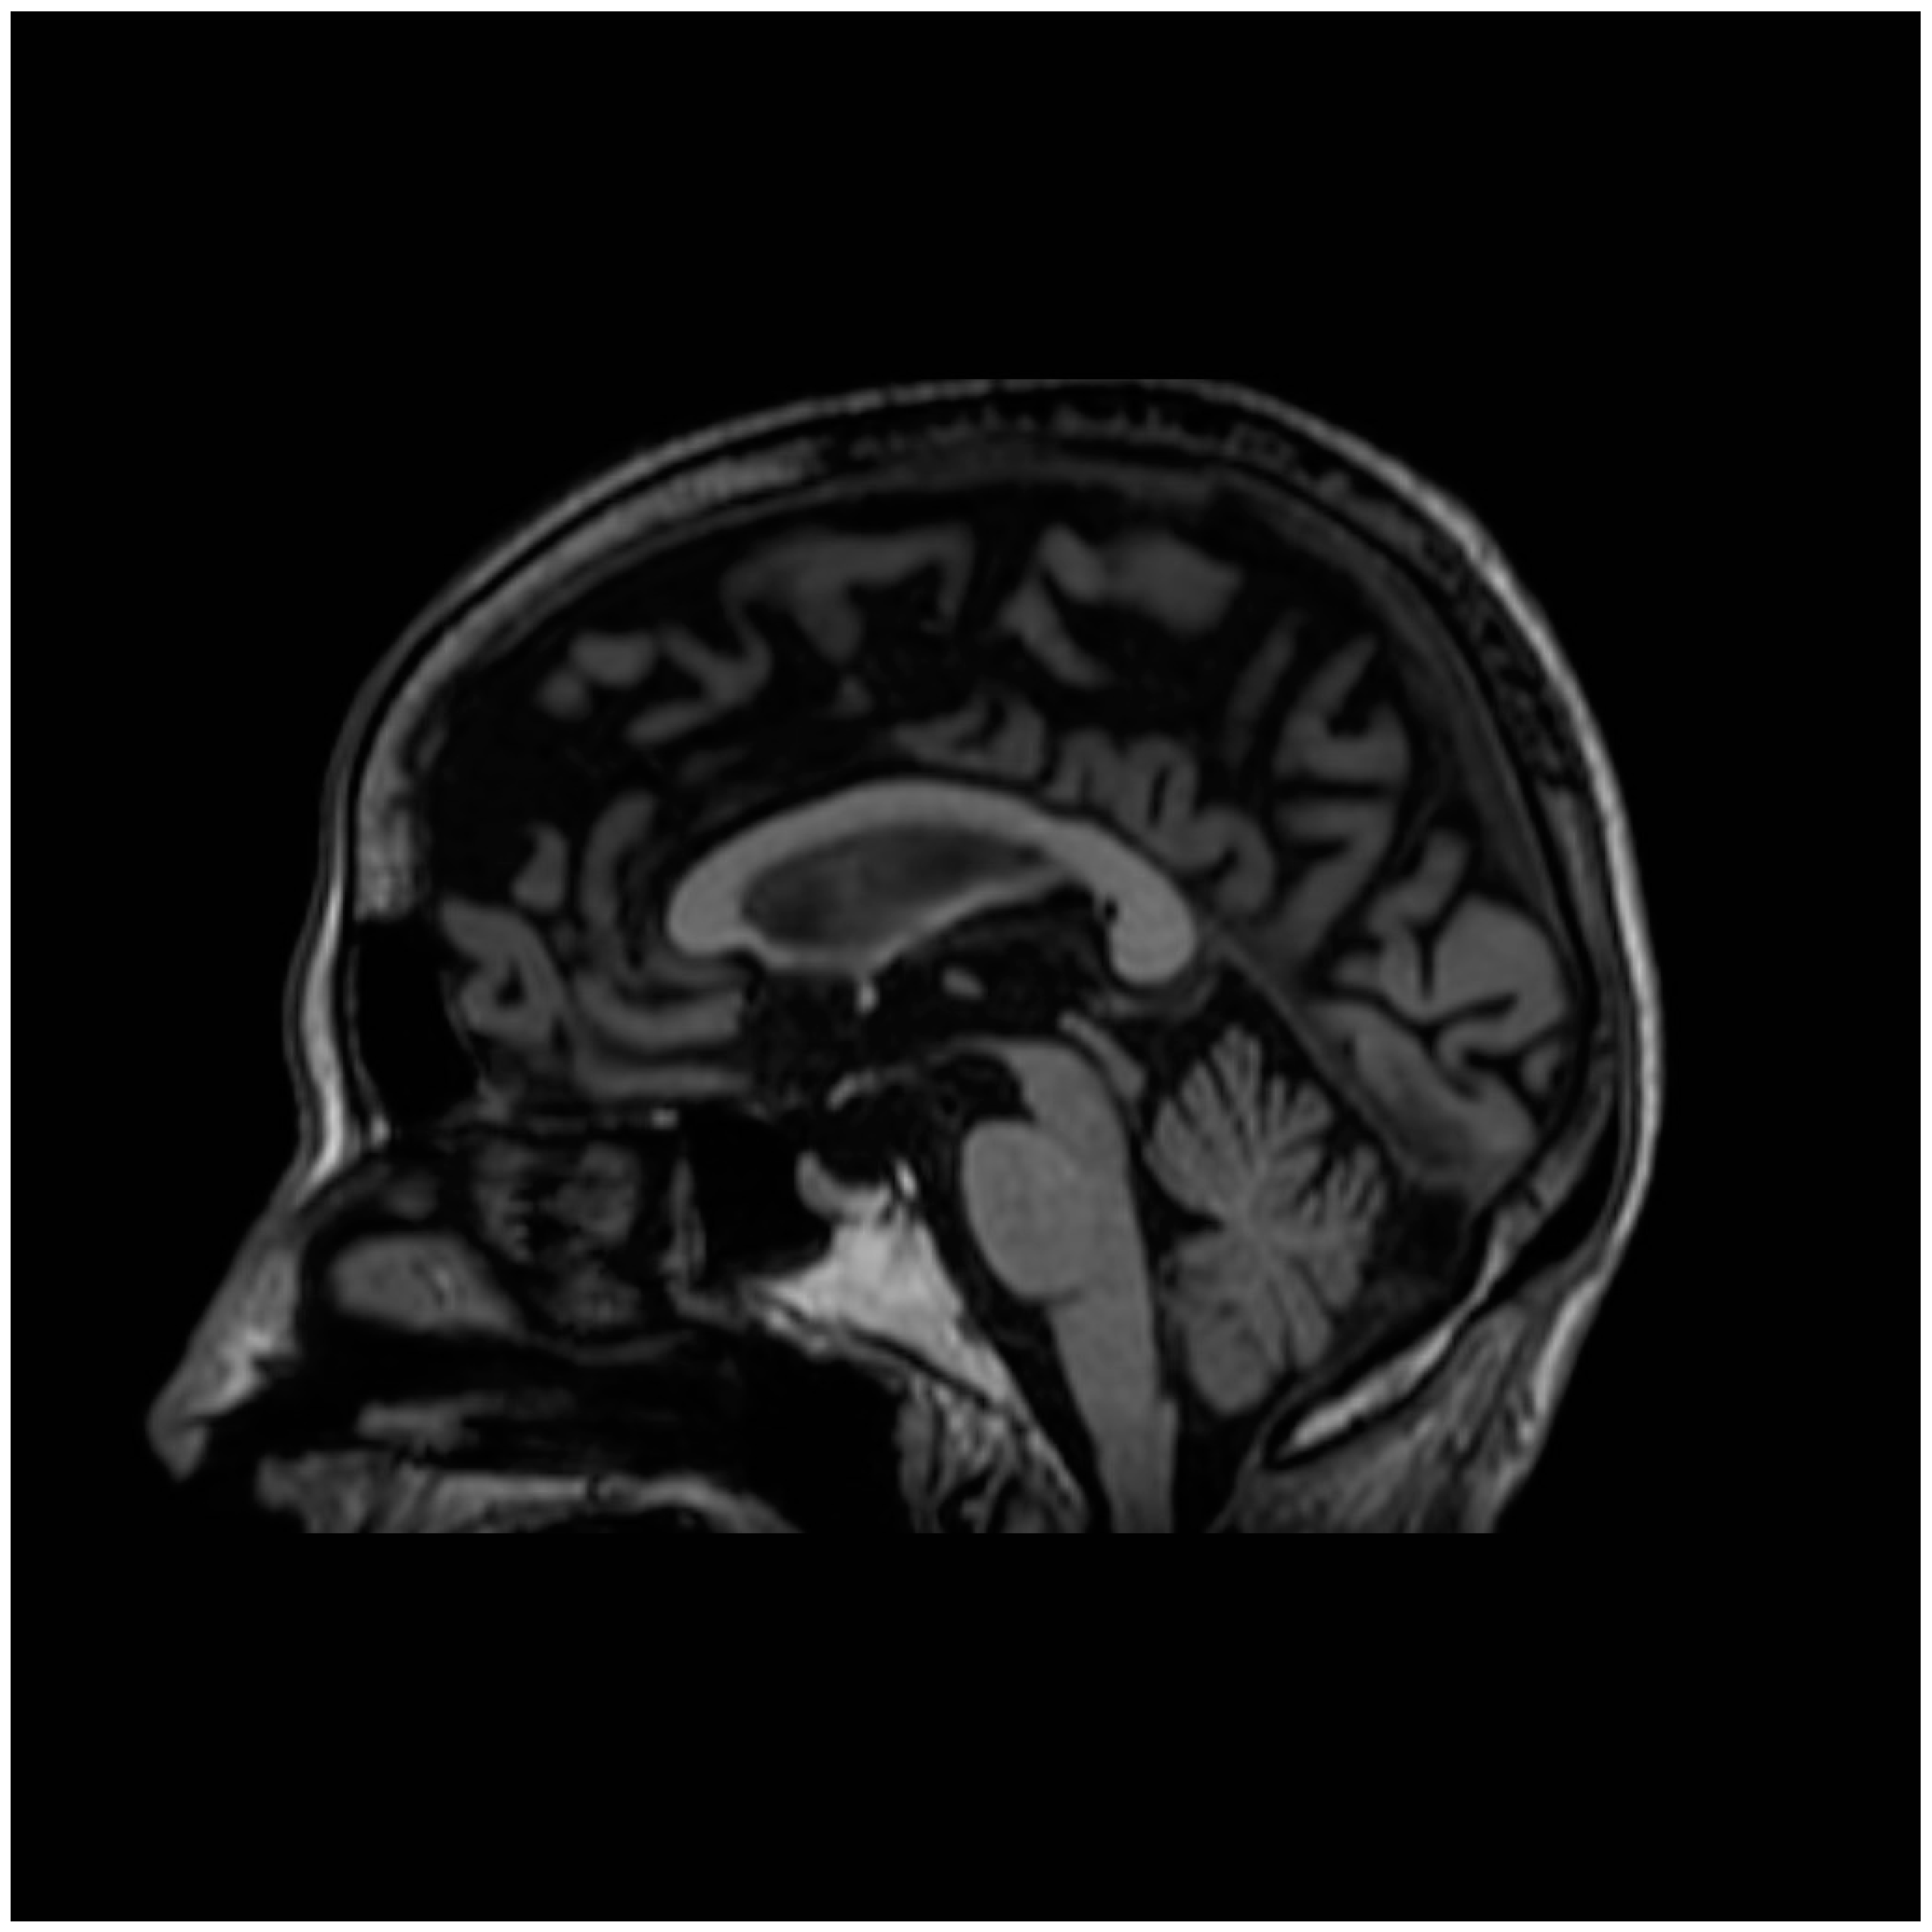

- Hummingbird sign: In midbrain atrophy, the thinning of the midbrain tegmentum and the widening of the superior cerebellar peduncles contribute to this distinctive imaging pattern. The superior cerebellar peduncles extend upward, and when combined with the atrophy of the midbrain, they create a silhouette reminiscent of a hummingbird (Figure 1) [25].

Figure 1. Sagittal MRI T1 scan demonstrating characteristic hummingbird sign in PSP. - (iii)